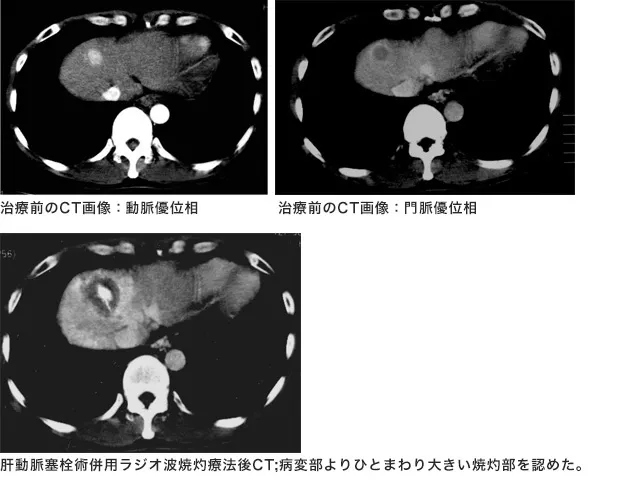

ラジオ波焼灼療法(RFA)・経皮的エタノール注入療法(PEI)

この治療の適応となる患者様はがん病変が切除不能または患者様が切除を希望しない、病変が3cm3個以内あるいは5cm以内単発、肝機能が悪くないことや出血傾向がないなどの制限がありますが、治療部位の再発はかなり低く、成績の良い治療です。

当院では患者様それぞれの状況に対して臨機応変に適応拡大して治療を行っています。また、それにともない肝動脈塞栓療法との併用や人工胸水、人工腹水併用下ラジオ波焼灼療法も行っております。

ラジオ波施行例